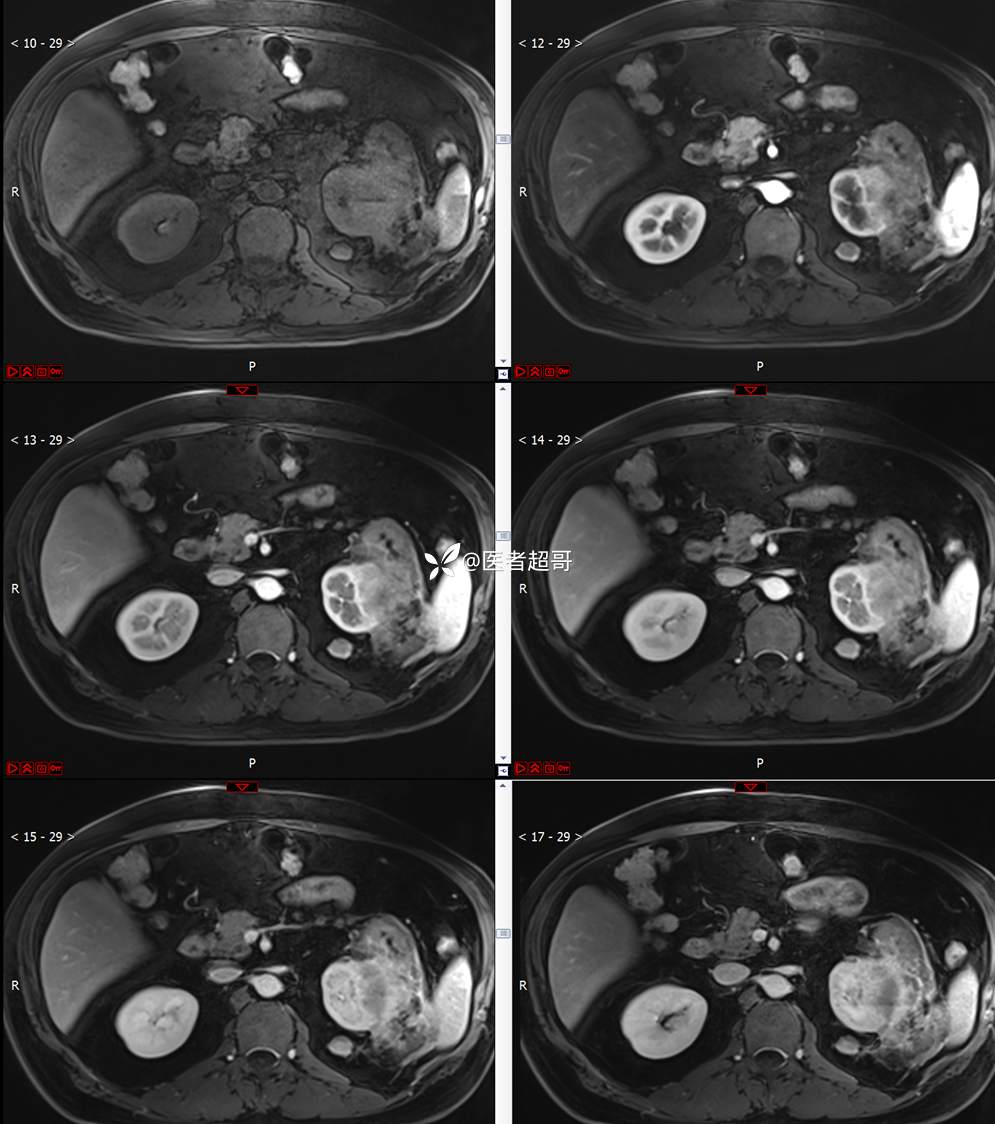

主 诉:查体发现左肾肿物9天。

现病史:患者9天前于附属医院行常规腹部CT检查时,发现左肾占位性病变并肾周脂间隙软组织增多,自述无明显腰腹部不适,无尿频、尿急、尿痛及肉眼血尿,未予特殊治疗,患者近期无头晕头迷,胸闷气急,腹胀腹泻及其他部位明显不适,遂至我院就诊,门诊以“肾肿物”收入院,患者自发病以来,精神可,睡眠饮食可,大便正常,体重无明显减轻。